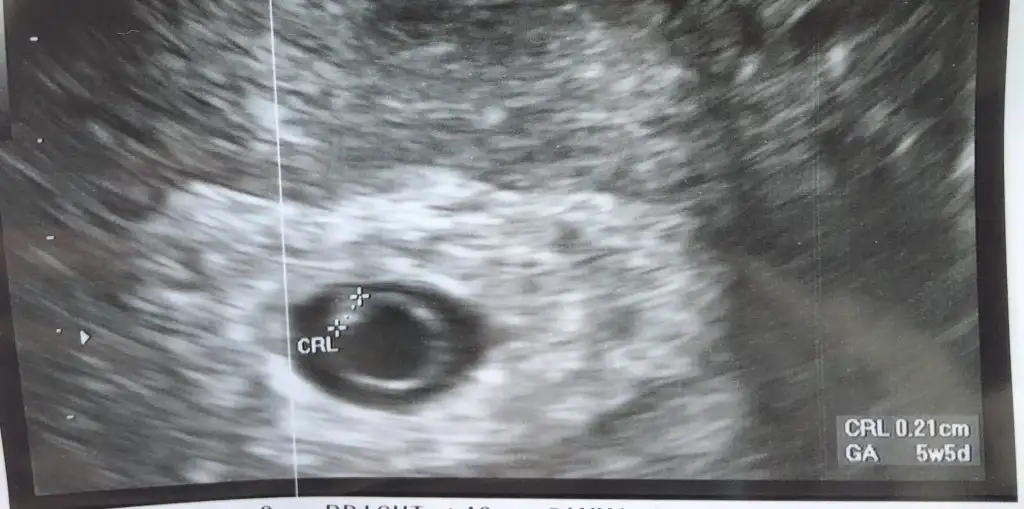

Kese bu şekilde canım ama o kadar moralimi bozdu ki böyle umudumu bitirdiSeni en iyi bilen tup bebek doktorun tabiki de benim doktorum ilk kese gordugunde sagliksiz olsa kese bozuk olurdu demisti kendini belli eder demisti inşallahh haftaya sagsalim duyarsiniz kalbini

Kesen ne kadar da guzel gozukuyor maşallah inşallahh sagsalim duyarsinizKese bu şekilde canım ama o kadar moralimi bozdu ki böyle umudumu bitirdi